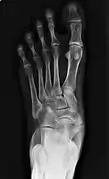

X-ray of the foot showing an accessory navicular bone

An accessory navicular bone is an accessory bone of the foot that occasionally develops abnormally in front of the ankle towards the inside of the foot. This bone may be present in approximately 2-21% of the general population and is usually asymptomatic.[1][2][3] When it is symptomatic, surgery may be necessary.